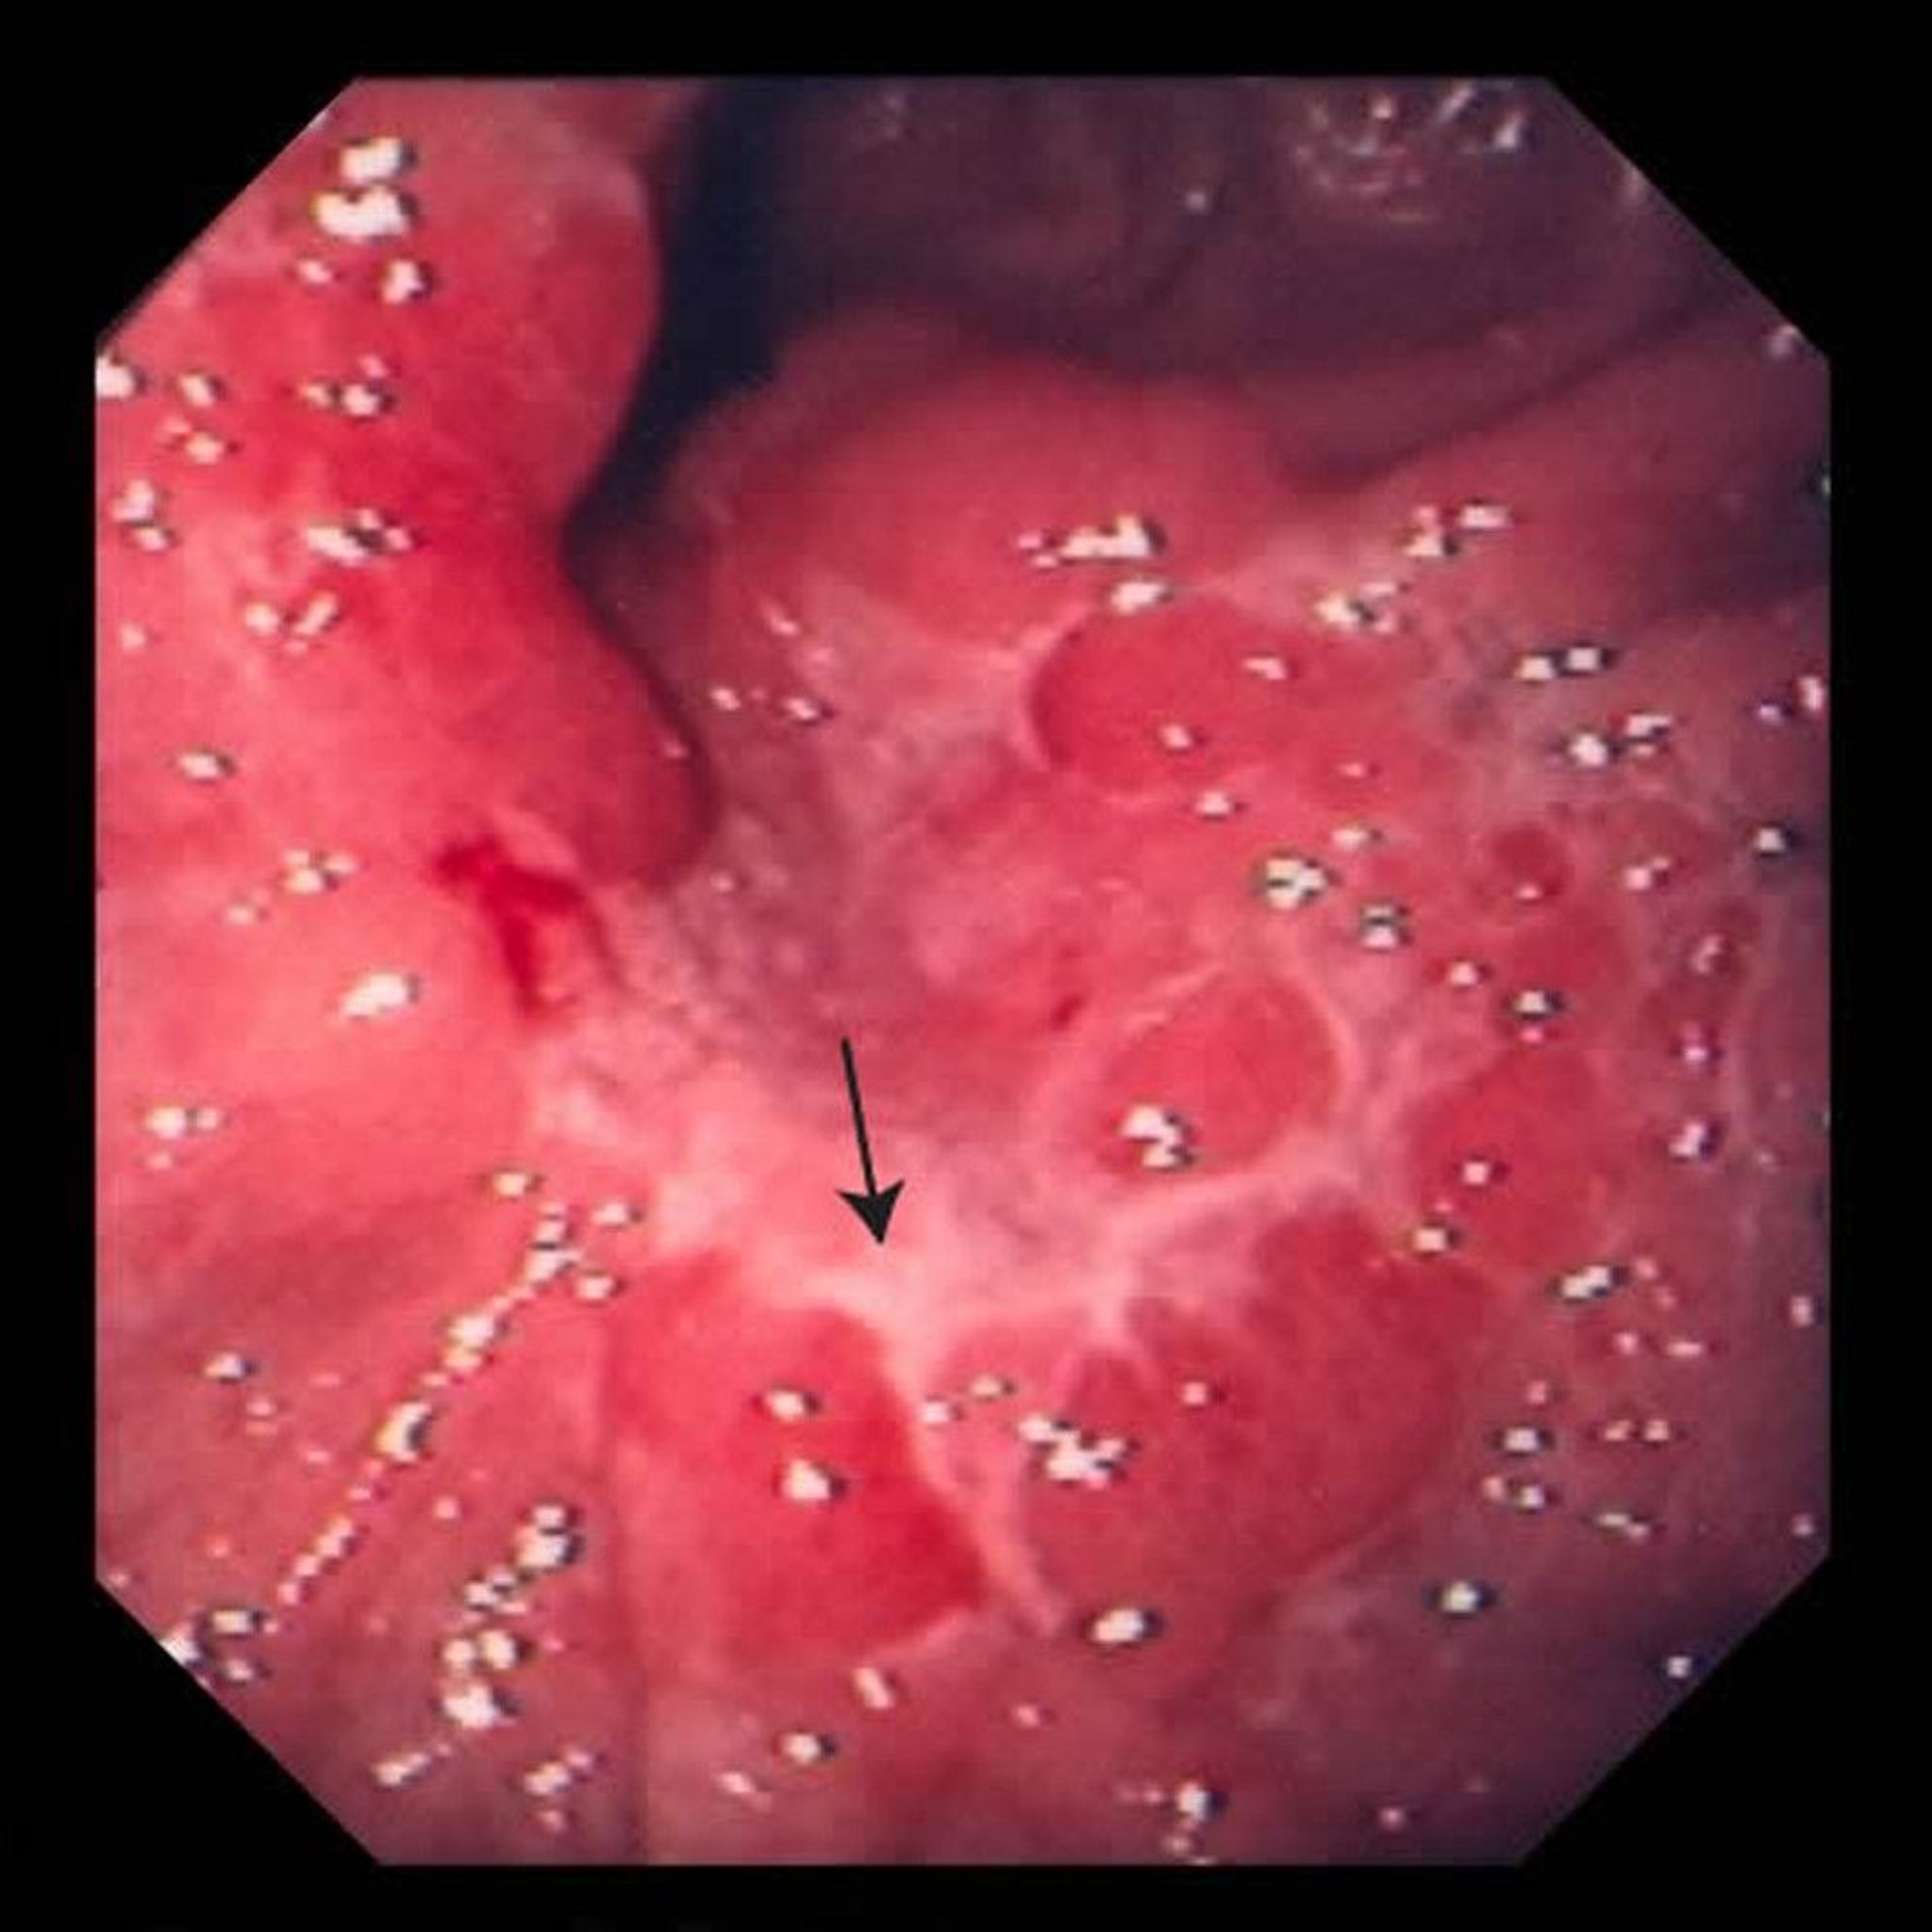

This image shows an ulcer in the stomach (arrow). After a biopsy, doctors determined it was an adenocarcinoma.

Image provided by David M. Martin, MD.